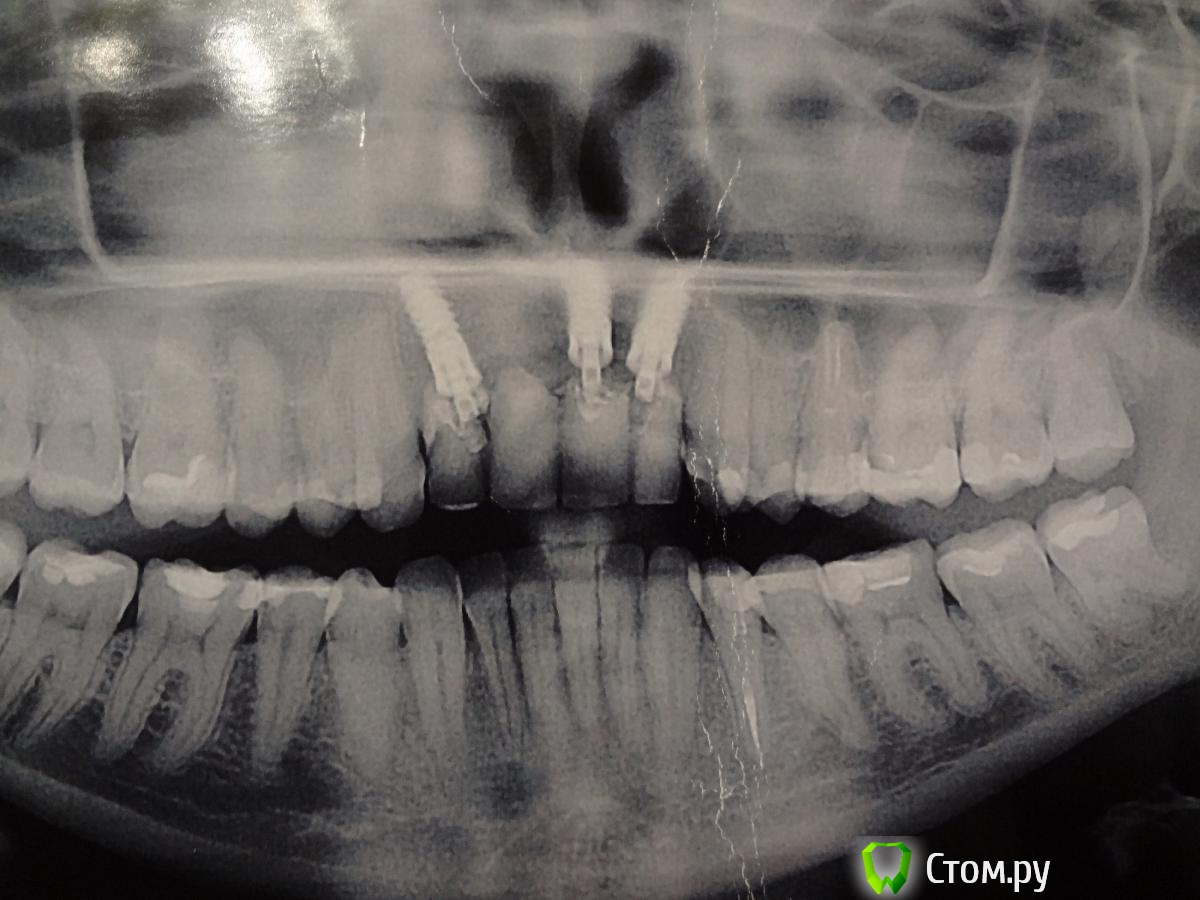

Яркая брюнетка Опубликовано 6 декабря, 2013 Поделиться Опубликовано 6 декабря, 2013 (изменено) Здравствуйте.У меня отсутствуют 4 верхних передних зуба. Поставили на их место 3 импланта Impla.Случай у меня довольно не простой, так как это уже 3 моя имплантация , которая наконец то оказалась удачной. До этого костная ткань была разрушена кистами на корнях зубов , были свищи, неоднократные чистки и в итоге только третья имплантация после подсадки костной ткани оказалась удачной.Сейчас у меня стоит мост из 4-х зубов на 3-х имплантах. Но это довольно не прочная конструкция. Пластмассовые зубы и пластмассовые абатменты. Ими я кусаю только мягкие продукты, а то не выдержат.К сожалению, сейчас по финансовым соображениям не могу поставить постоянную конструкцию (хочу из диоксида циркония). Но переживаю,что из за недостаточной нагрузки на зубы и импланты кость вокруг имплантов начнет убывать С временной конструкцией хожу уже 9 месяцев.Скажите ,пожайлуста, правда ли при недостаточной нагрузке кость вокруг импланта разрушается? И как быстро это происходит? Ведет ли это к потере имплантов? Изменено 6 декабря, 2013 пользователем Яркая брюнетка Ссылка на комментарий

Яркая брюнетка Опубликовано 7 декабря, 2013 Автор Поделиться Опубликовано 7 декабря, 2013 (изменено) В электронном виде не было, поэтому сфотографировала распечатанный электронный вариант. Изменено 7 декабря, 2013 пользователем Яркая брюнетка Ссылка на комментарий

Яркая брюнетка Опубликовано 7 декабря, 2013 Автор Поделиться Опубликовано 7 декабря, 2013 Из фото видно как у меня атрофировалась десна из за этих многочисленных операций. Постоянный мост нужно будет делать с искусственной десной( Ссылка на комментарий